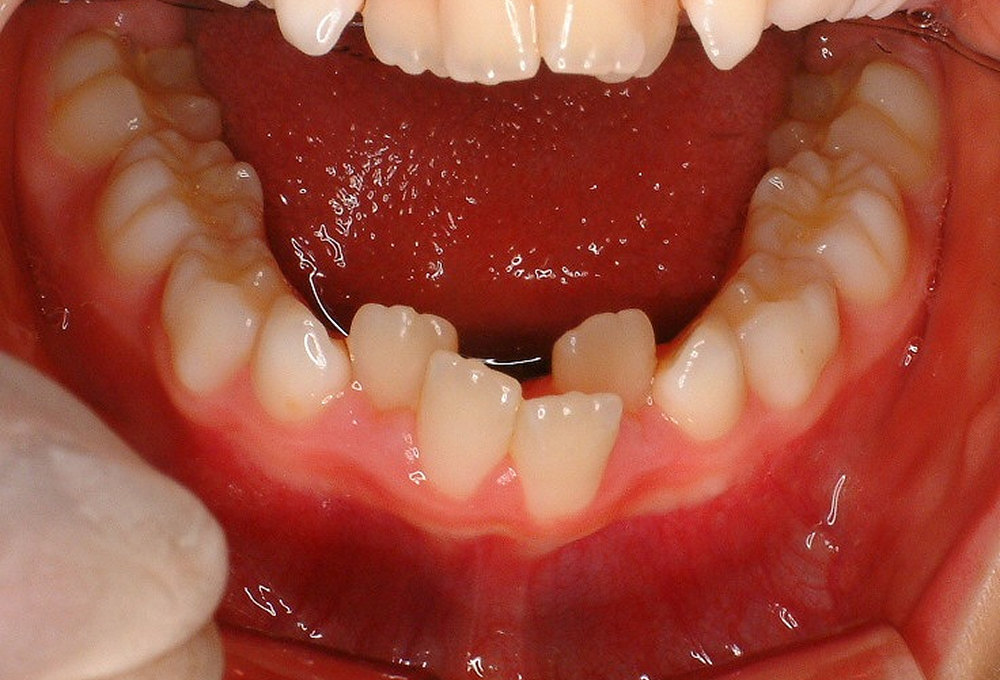

③術前 下顎